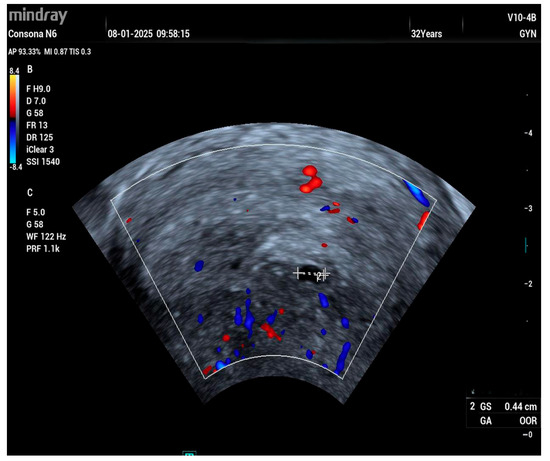

A 32-year-old woman, gravida 1 para 0, was referred to our clinic at six weeks gestation with a suspected ectopic pregnancy. She had previously undergone hysteroscopic surgery to remove a uterine septum 3 years ago. A transvaginal ultrasound showed a 0.44 mm pseudogestational sac in the uterus (Figure 1).

Figure 1. Pseudo sac in the uterine cavity.

Compared to electrosurgical instruments and other laser systems, the Ho:YAG laser is associated with a shallower depth of tissue penetration, resulting in less thermal injury and reduced collateral damage [27,28,29,30]. This is particularly beneficial in procedures such as hysteroscopic metroplasty, where minimizing the risk of uterine perforation is critical, especially in women desiring future fertility. The limited lateral thermal spread also supports faster endometrial healing and may help reduce the risk of postoperative intrauterine adhesions (Figure 1) [31].